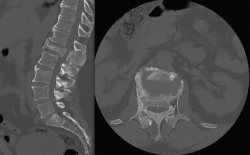

Como estudio previo a la cirugía se realiza una tomografía axial computarizada (TAC) de columna lumbosacra (Figura 2), confirmándose el aplastamiento y la retropulsión del cuerpo de L1. Si bien la vértebra muestra una morfología peculiar, con una hipertrofia de los elementos posteriores y aparentes focos escleróticos y líticos en L1, además se observa un pequeño arrancamiento de la esquina anterior del platillo superior de L3.

Figura 2. Tomografía axial computarizada de columna lumbosacra. Corte sagital: aplastamiento del cuerpo vertebral L1, ocupación del canal medular e hipertrofia de la apófisis espinosa. Corte axial: cuerpo vertebral con morfología heterogénea.